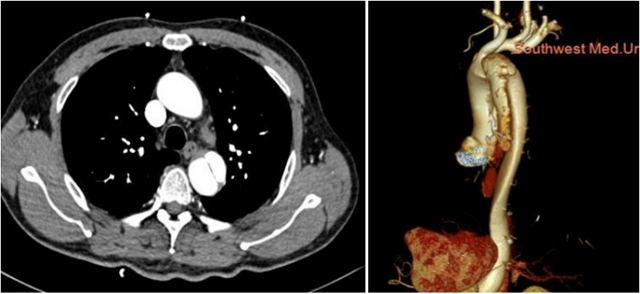

术前检查

张三的家人迅速将他送往西南医科大学附属中医医院,这一举动挽救了他的生命。接诊医生通过对症状的判断迅速启动了胸痛三联征“一站式”CT检查(这是一种通过注射造影剂进行的CT检查技术,可以详细观察胸部大血管的结构)。

经过检查,医生迅速诊断出张三患有主动脉夹层,需要立即行手术干预。最终张三接受了手术治疗,成功挽救了生命。如果没有及时的“一站式”CT检查,他的情况会迅速恶化,将危及生命。

“一站式”CT检查

胸痛三联征“一站式”CT检查是指通过一次扫描、一次注射造影剂可同时显示冠状动脉、肺动脉及主动脉三种血管的图像,有助于早期、快速诊断,同时可以最大程度降低辐射剂量。因此已成为目前评估急性胸痛患者的首选检查方法。

2.主动脉夹层的检测:这一检查能够清楚地显示主动脉的解剖结构,帮助医生观察主动脉夹层并确定其位置和严重程度,及时进行干预。